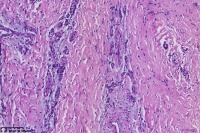

足趾包块,血管瘤?软纤维瘤?

性别

女

年龄

22岁

临床诊断

足趾包块

一般病史

足趾包块1月

标本名称

大体所见

结节一个,1.1X1X0.6Cm³,切面半透明状,质软。

毛细血管瘤。

血管纤维瘤

化脓性肉芽肿,血管瘤的一个亚型